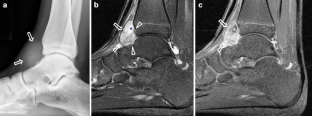

Synovium is the thin membranous lining of a joint. It produces synovial fluid, which lubricates and nourishes the cartilage and bone in the joint capsule. Synovial diseases in children can be classified as normal structures as potential sources of pathology (synovial folds: plicae, infrapatellar fat pad clefts), noninfectious synovial proliferation (juvenile idiopathic arthritis, hemophilic arthropathy, lipoma arborescens, synovial osteochondromatosis, pigmented villonodular synovitis, reactive synovitis), infectious synovial proliferation (pyogenic arthritis, tuberculous arthritis), deposition disease (gouty arthropathy), vascular malformation, malignancy (metastasis) and intra-/periarticular cysts and cyst-like structures. Other intra-articular neoplasms, such as intra-articular synovial sarcoma, can mimic synovial disease in children.

Fig. 2